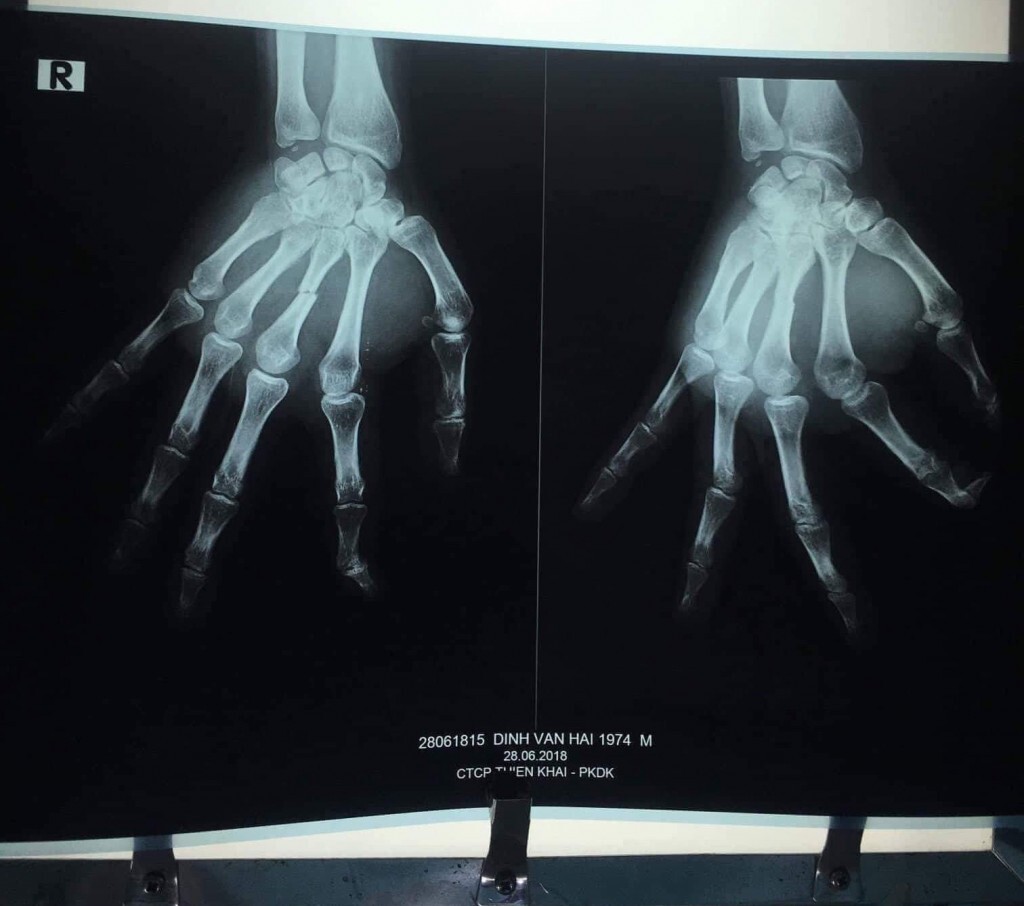

Đây là 1 trong các phim chụp X-quang của anh Đinh Văn Hải - một người bị tật ở Lâm Đồng. Anh gãy nhiều xương trên cơ thể do một nhóm người được cho là an ninh - công an tỉnh này đánh khi anh tới thăm cô Đỗ Thị Minh Hạnh ở Di Linh trở về. Có những sự tàn ác của người cộng sản vượt qua mức tưởng tượng. Xin xem thêm bài viết trên fb cô Ngô Thị Hồng Lâm.